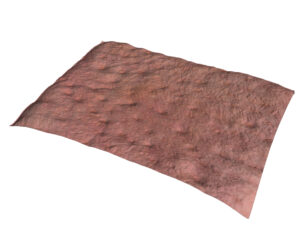

Vous pouvez également réaliser des acquisitions en 3D de la surface de la peau. Grâce à une technique appelée stéréo photométrique, le système C-Cube analyse plusieurs images dans différentes conditions d’éclairage. Le logiciel estime les normales de surface. Combiné à une calibration géométrique, il produit des informations d’élévation à chaque pixel.

Grâce à sa capacité unique de mesure de paramètres 3D, il est possible de mesurer l’élévation des boutons avec la hauteur du pic (Sp) et l’amplitude totale (Sz). Un effet du produit testé pourra être prouvé si l’élévation du pic diminue dans le temps.

Élévation des boutons Hauteur des pics et amplitude

Évaluation de la rugosité

Le C-Cube est indéniablement la meilleure option pour évaluer les changements les plus subtils. Au-delà de la mesure de l’élévation des boutons, il est capable d’observer de très petits signes d’acné avant qu’ils ne s’aggravent avec l’inflammation. Cela revient à mesurer la texture de la peau, invisible à l’œil nu.